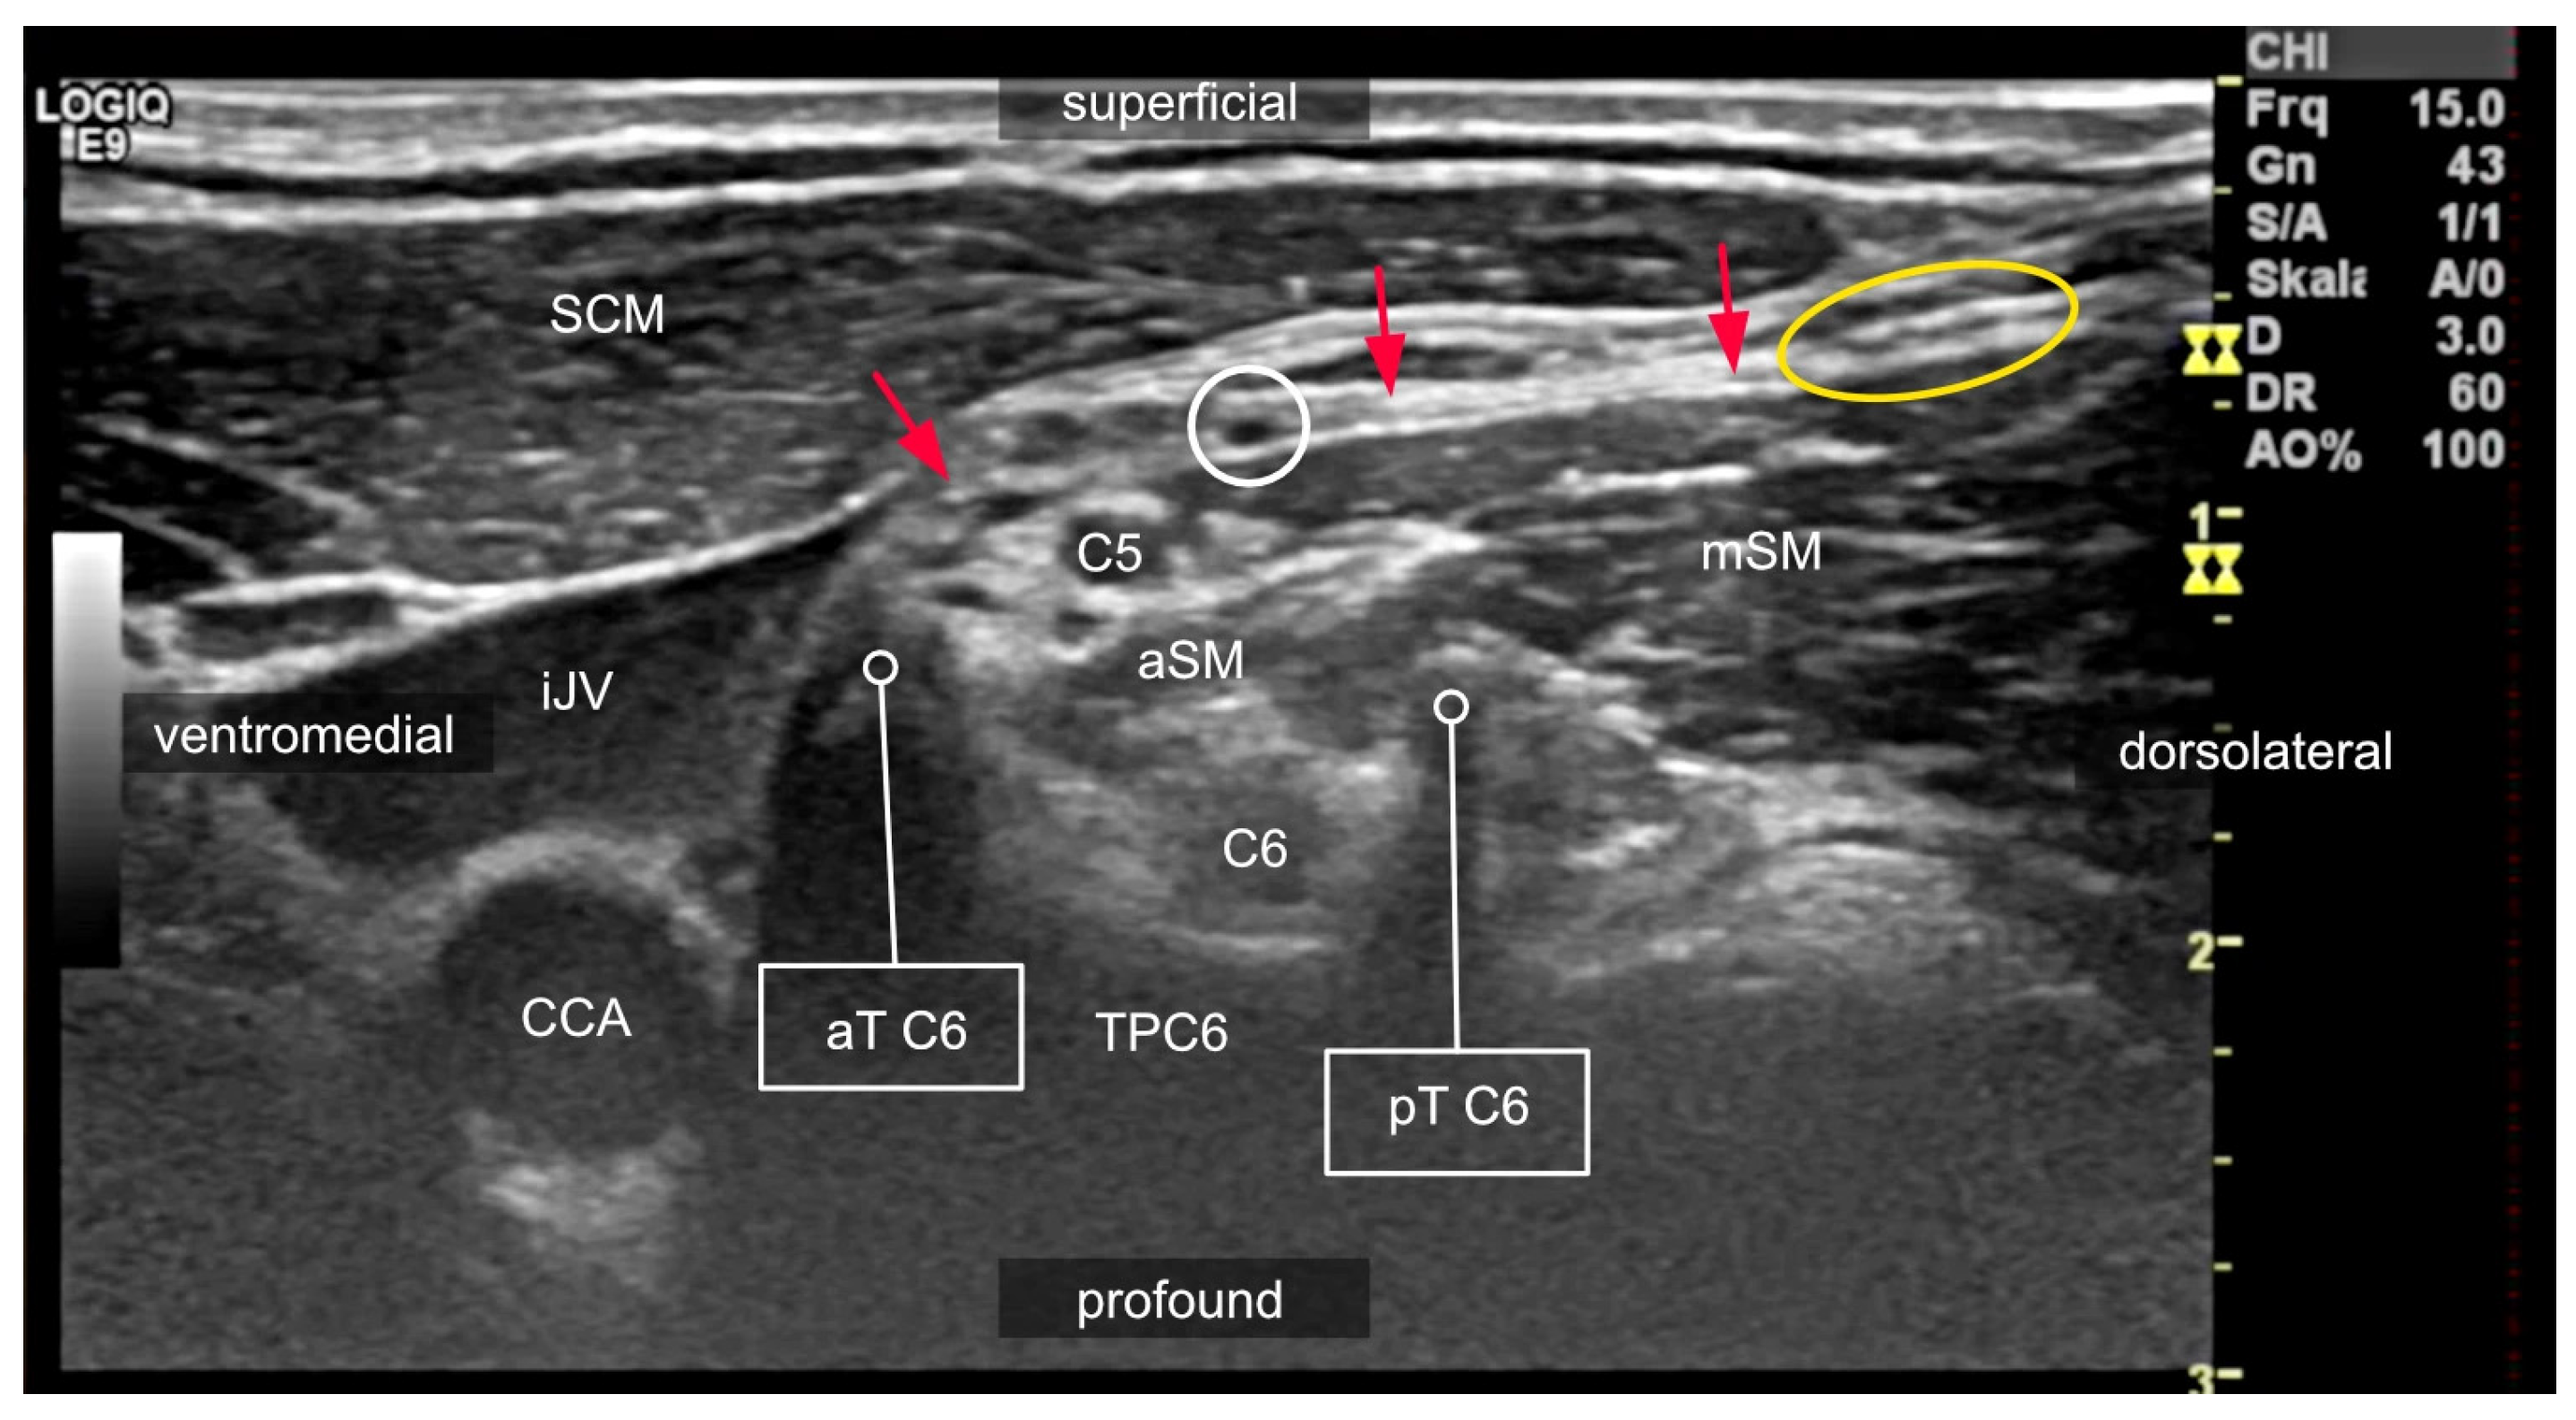

2. Relevant Anatomy for Interscalene Brachial Plexus Blocks

2.2. Anatomical Variations in the Scalene Gap

2.3. Variants of the Course of the Ventral Rami

2.4. Compartments of the Lateral Neck and Their Relevance to Side Effects

3.2. Interscalene Access

3.6. The Role of Ultrasound